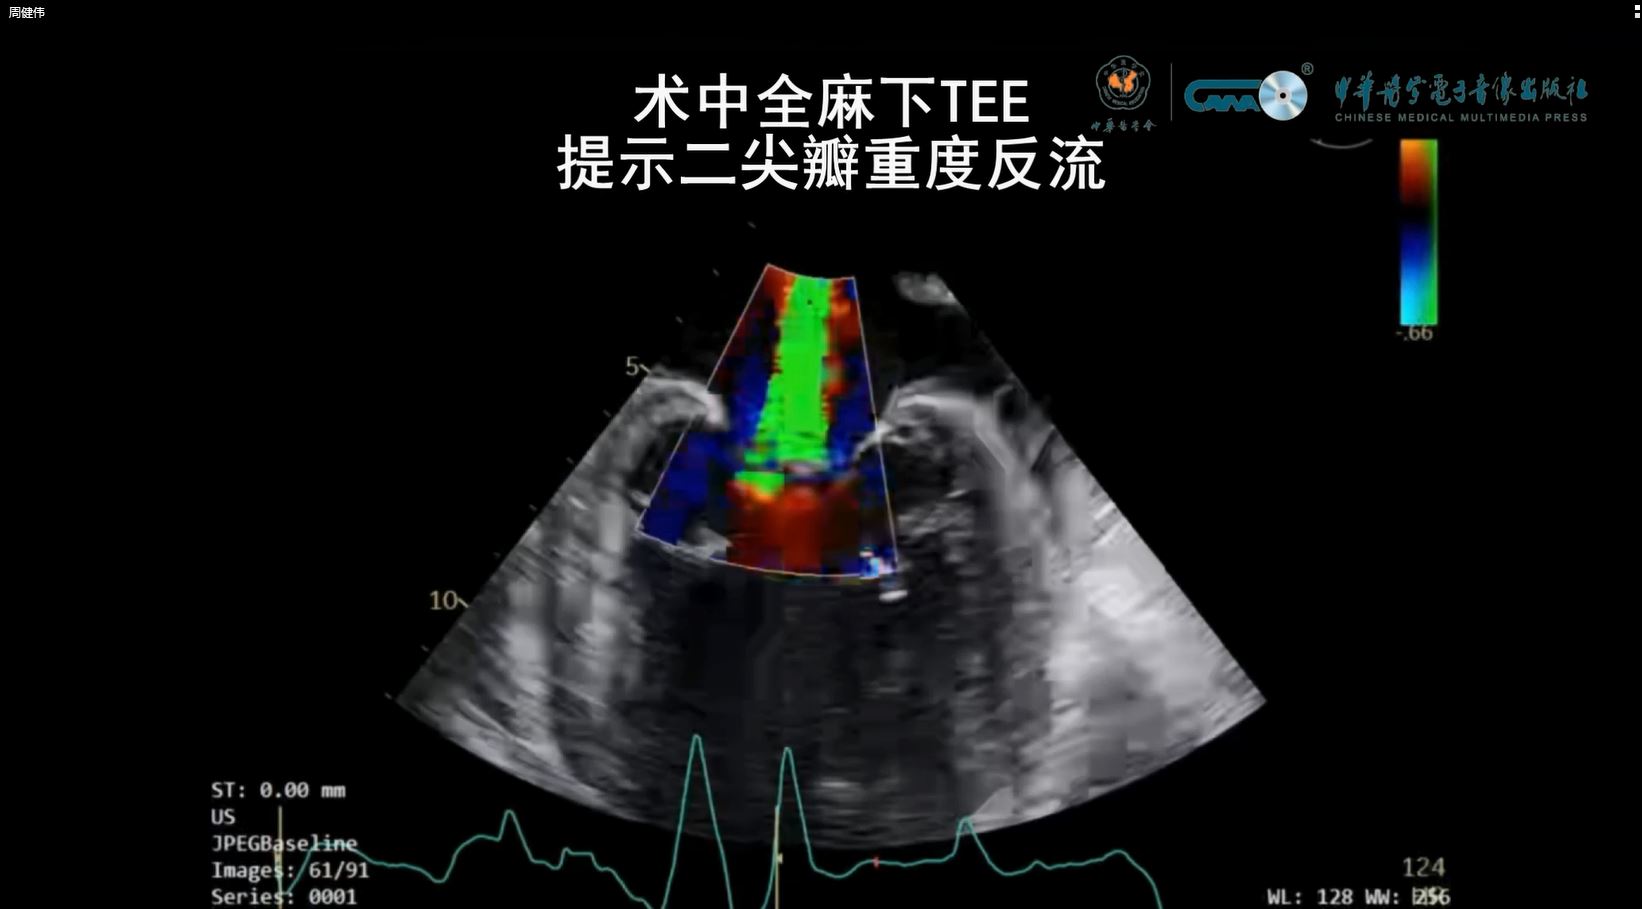

表现为重度二尖瓣反流的低流量低压差重度主动脉瓣狭窄患者术中术后经食管超声心动图及术中造影动态影像视频

周健伟, 顾辰昊, 申雪纯, 杨菲, 何胜虎, 徐冰

中华诊断学电子杂志 2026 , 14 (01) : 49 -52 .